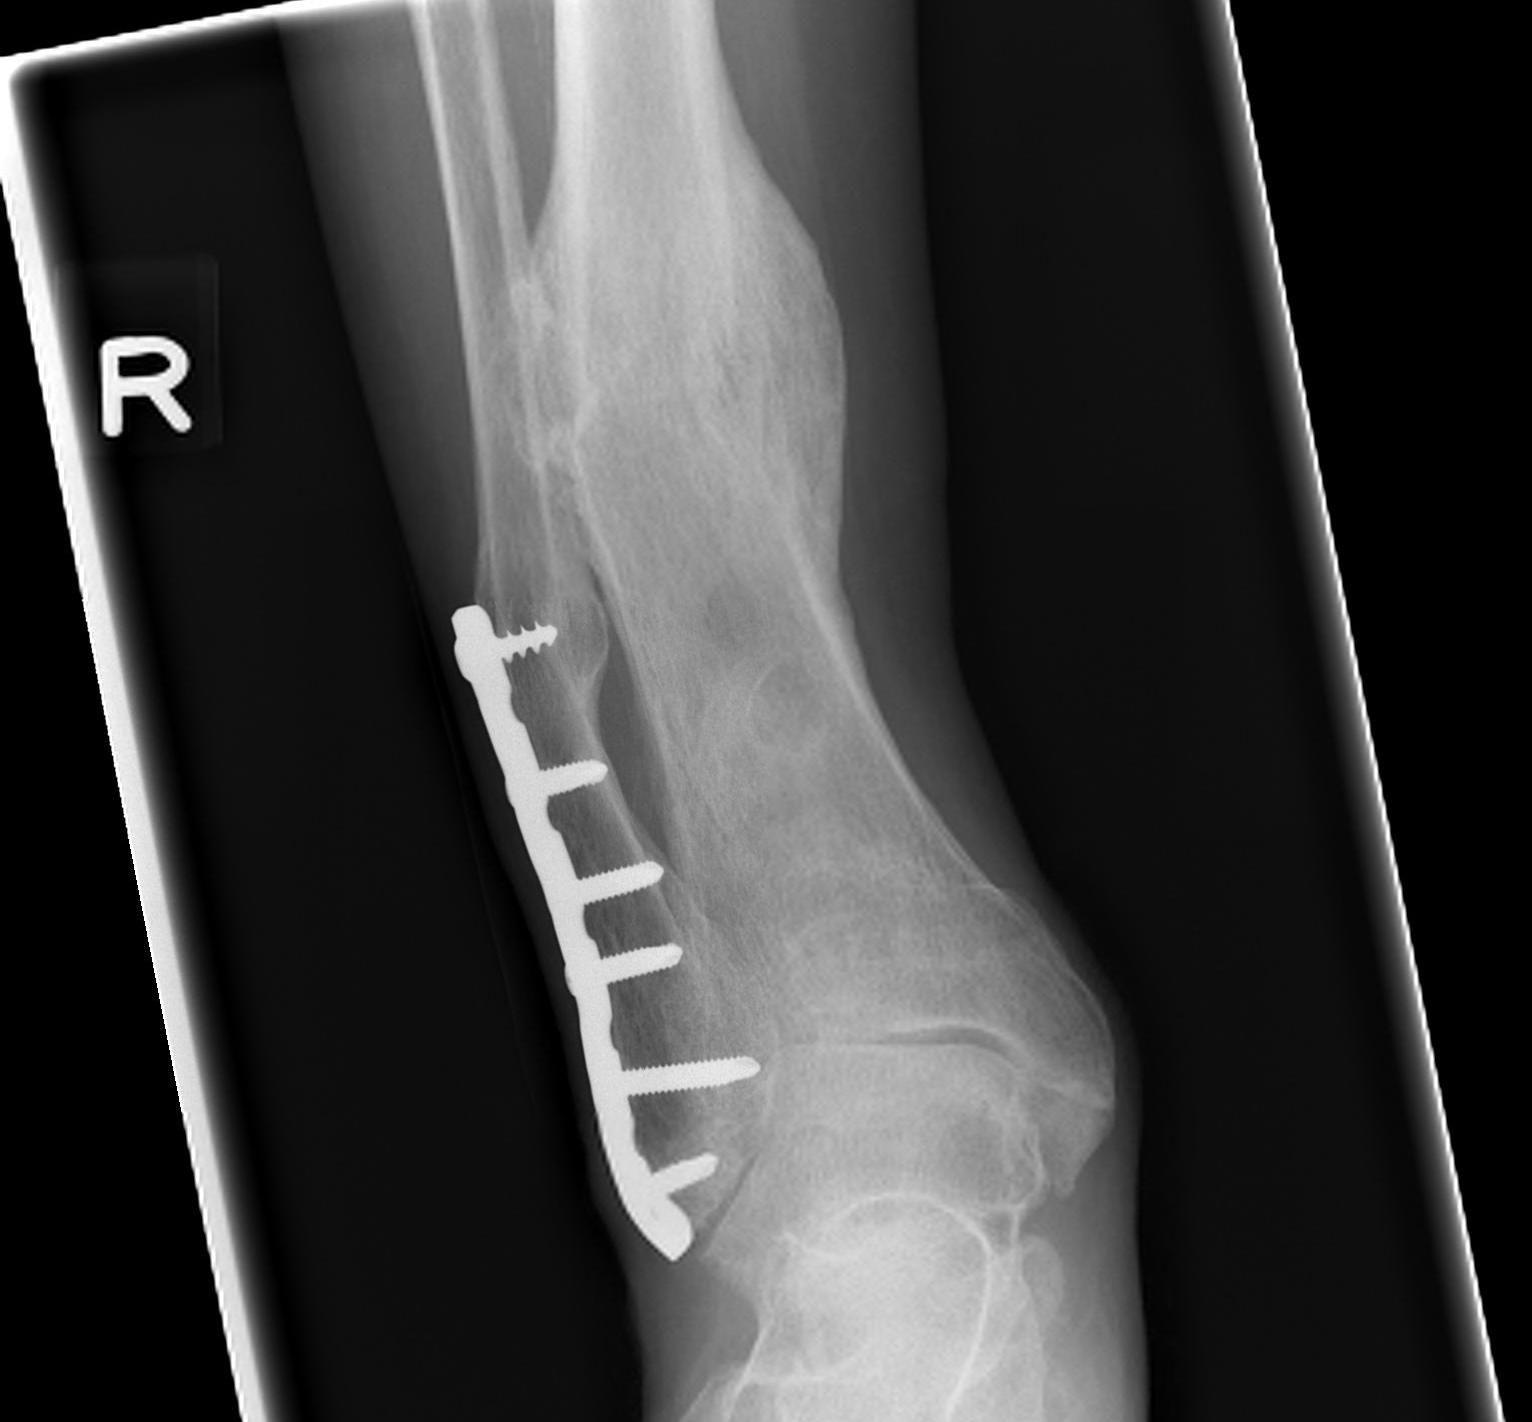

B. Distal Tibial ORIF with plate

Indications

- too distal to nail

- very comminuted / unstable

- intra-articular extension

Technique

1. Consider fixing the fibula

- will aid reduction / avoid malunion

- help control very unstable fractures

2. Anatomically contoured plates

- options of medial plate v anterolateral plate

- medial plate for varus deformity

- anterolateral plate for valgus deformity